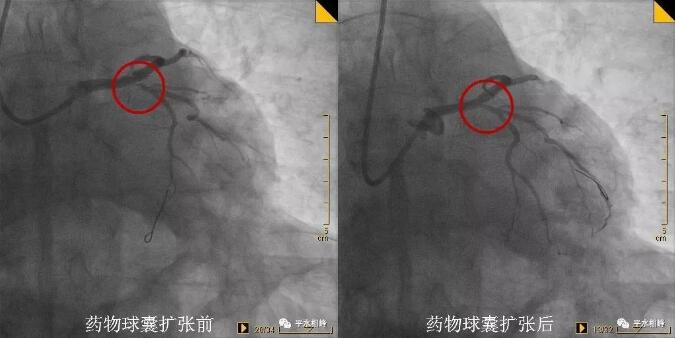

病例一 53岁中年男性,胸闷不适1月入院。1年前曾行支架植入术,复查冠脉造影提示支架内再狭窄。于支架内行药物球囊扩张术,术后效果良好。 病例二 69岁老年男性,突发胸痛1.5小时入院。既往有高血压、糖尿病病史。反复冠脉造影提示回旋支开口较前狭窄加重,行药物球囊扩张术,术后未再发作胸痛。 病例三 53岁中年男性,发作性胸部不适1月入院。新发现高血压、糖尿病。冠脉造影提示第一对角支粗大,开口狭窄80%,行药物球囊扩张术,术后效果良好。 什么是药物球囊扩张术 据高希春主任医师介绍,药物涂层球囊(DCB),是在传统球囊上基础上,均匀地涂上紫杉醇和造影剂(碘普罗胺)的混合基质,医生用30~45秒的时间扩张球囊,把药物贴粘至心脏冠状动脉的病变部位,起抗细胞增殖的作用,然后球囊和导管撤出体外,患者体内不留任何异物。 与目前治疗冠心病的主要临床手段--药物支架相比,药物球囊具有显著优势: ①在完成对病变血管的治疗后撤出体外,不留在人体内,能大大减轻血管内膜炎症反应,同时有效维持血管正常解剖结构,为患者保留必要的后续治疗机会。 ②没有支架的Polymer聚合物基质,同时无金属网格残留,在人体内不留异物,可明显减少血栓发生率,可将患者服用双联抗血小板凝聚药物的时间由药物支架的12个月以上缩短到1~3个月,可极大地降低患者出血的风险。 但并不是所有患者适合药物球囊,药物球囊主要适用于某些分叉病变、支架内再狭窄、小血管病变、弥漫性病变等药物支架疗效不佳或无法治疗患者。 药物球囊扩张技术以前只能在三甲及以上医院开展。随着药物涂层球囊技术在我院的开展,避免了患者必须转诊至市级以上大医院才能完成该手术的困境。 【科室简介】 心内科二病区目前共有医护人员23人,其中主任医师1名,副主任医师2名,主治医师6名,住院医师1名,其中硕士学历6人。科室擅长冠心病及其介入诊疗,心律失常及永久起搏器植入术,心内科常见疑难危重病例的诊治。 医院心内科介入团队2018年共完成冠脉造影+支架植入术1600多例,急诊PCI近二百例,均取得良好效果。 心内科二病区位于住院部五楼西区 护士站电话:0533-8228195 医生办公室:0533-822882